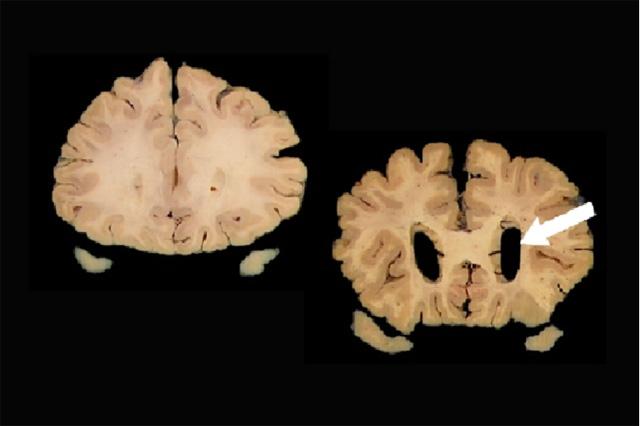

Researchers have focused primarily on three such biomarkers. Two are Alzheimer’s-related proteins, amyloid and tau. Amyloid forms clumps in brains, and tau forms skeins of filaments called neurofibrillary tangles. Both can be detected in cerebral spinal fluid or by specialized positron emission tomography, or PET, scans. The third marker, brain atrophy, can be seen with CT or MRI scans.

Because Alzheimer’s progresses slowly, the ACT participant autopsy results for amyloid, tau, and neurodegeneration were used to approximate AT(N) classification five years before death. The researchers considered evaluations over the five years before death to see whether the proxy AT(N) categorization at that time would predict dementia development in those five years.

The researchers found that 67% of those with the proxy A+T+(N)+ profile developed dementia in the next five years. But 33% did not.

“A+T+(N)+ is supposed to be the highest risk group,” Crane noted. “They have high levels of amyloid, high levels of tau, and have atrophy. Even in that group, a third never developed dementia.”

Dr. Caitlin Latimer, a neuropathologist at UW Medicine and a co-author on the paper, noted, “Although this study was limited to assessments of amyloid, tau, and neurodegeneration at autopsy, it serves as a reminder that these components are just one part of the complicated puzzle that is age-related cognitive decline. The AT(N) framework is valuable because it places living people on the spectrum of Alzheimer's disease neuropathologic change. This will allow us to better study the concept of resilience to this pathology and encourage the development of additional biomarkers necessary for the accurate prediction of who will go on to develop dementia.”